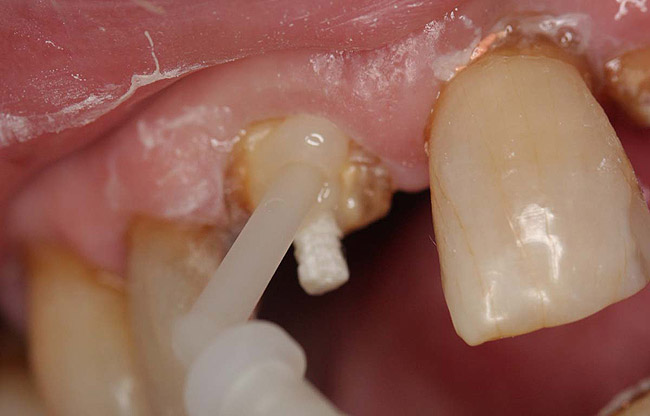

A terminally ill patient presented an abscess on the maxillary right central incisor. Endodontic treatment was completed with a composite restoration placed to restore the access hole. The crown fractured off within 1 week (Figure 15 and Figure 16). Gutta-percha was removed, and the canal prepared to accept a C-1 white post (Figure 17). The root was bonded with BRUSH and BOND™ (Parkell, www.parkell.com) and the post was cemented with a resin cement (Figure 18). Absolute Dentin core build-up material was applied (Figure 19). There are many different build-up materials, including glass ionomers such as Ketac-Silver™ (3M ESPE, www.3mespe.com) or Miracle Mix® (GC America, www.gcamerica.com), pastes that are mixed such as Zenith (Carson Dental, www.carsondental.com), and automix syringes such as Absolute Dentin. The material was of a consistency that allows placement without sagging or running (Figure 20). It was light-cured and prepared for temporization (Figure 21) and the final all-composite restoration was delivered (Figure 22).

Figure 17  The root canal was prepared to accept a post.

Figure 17

Figure 18  The post was cemented with bonded resin cement.